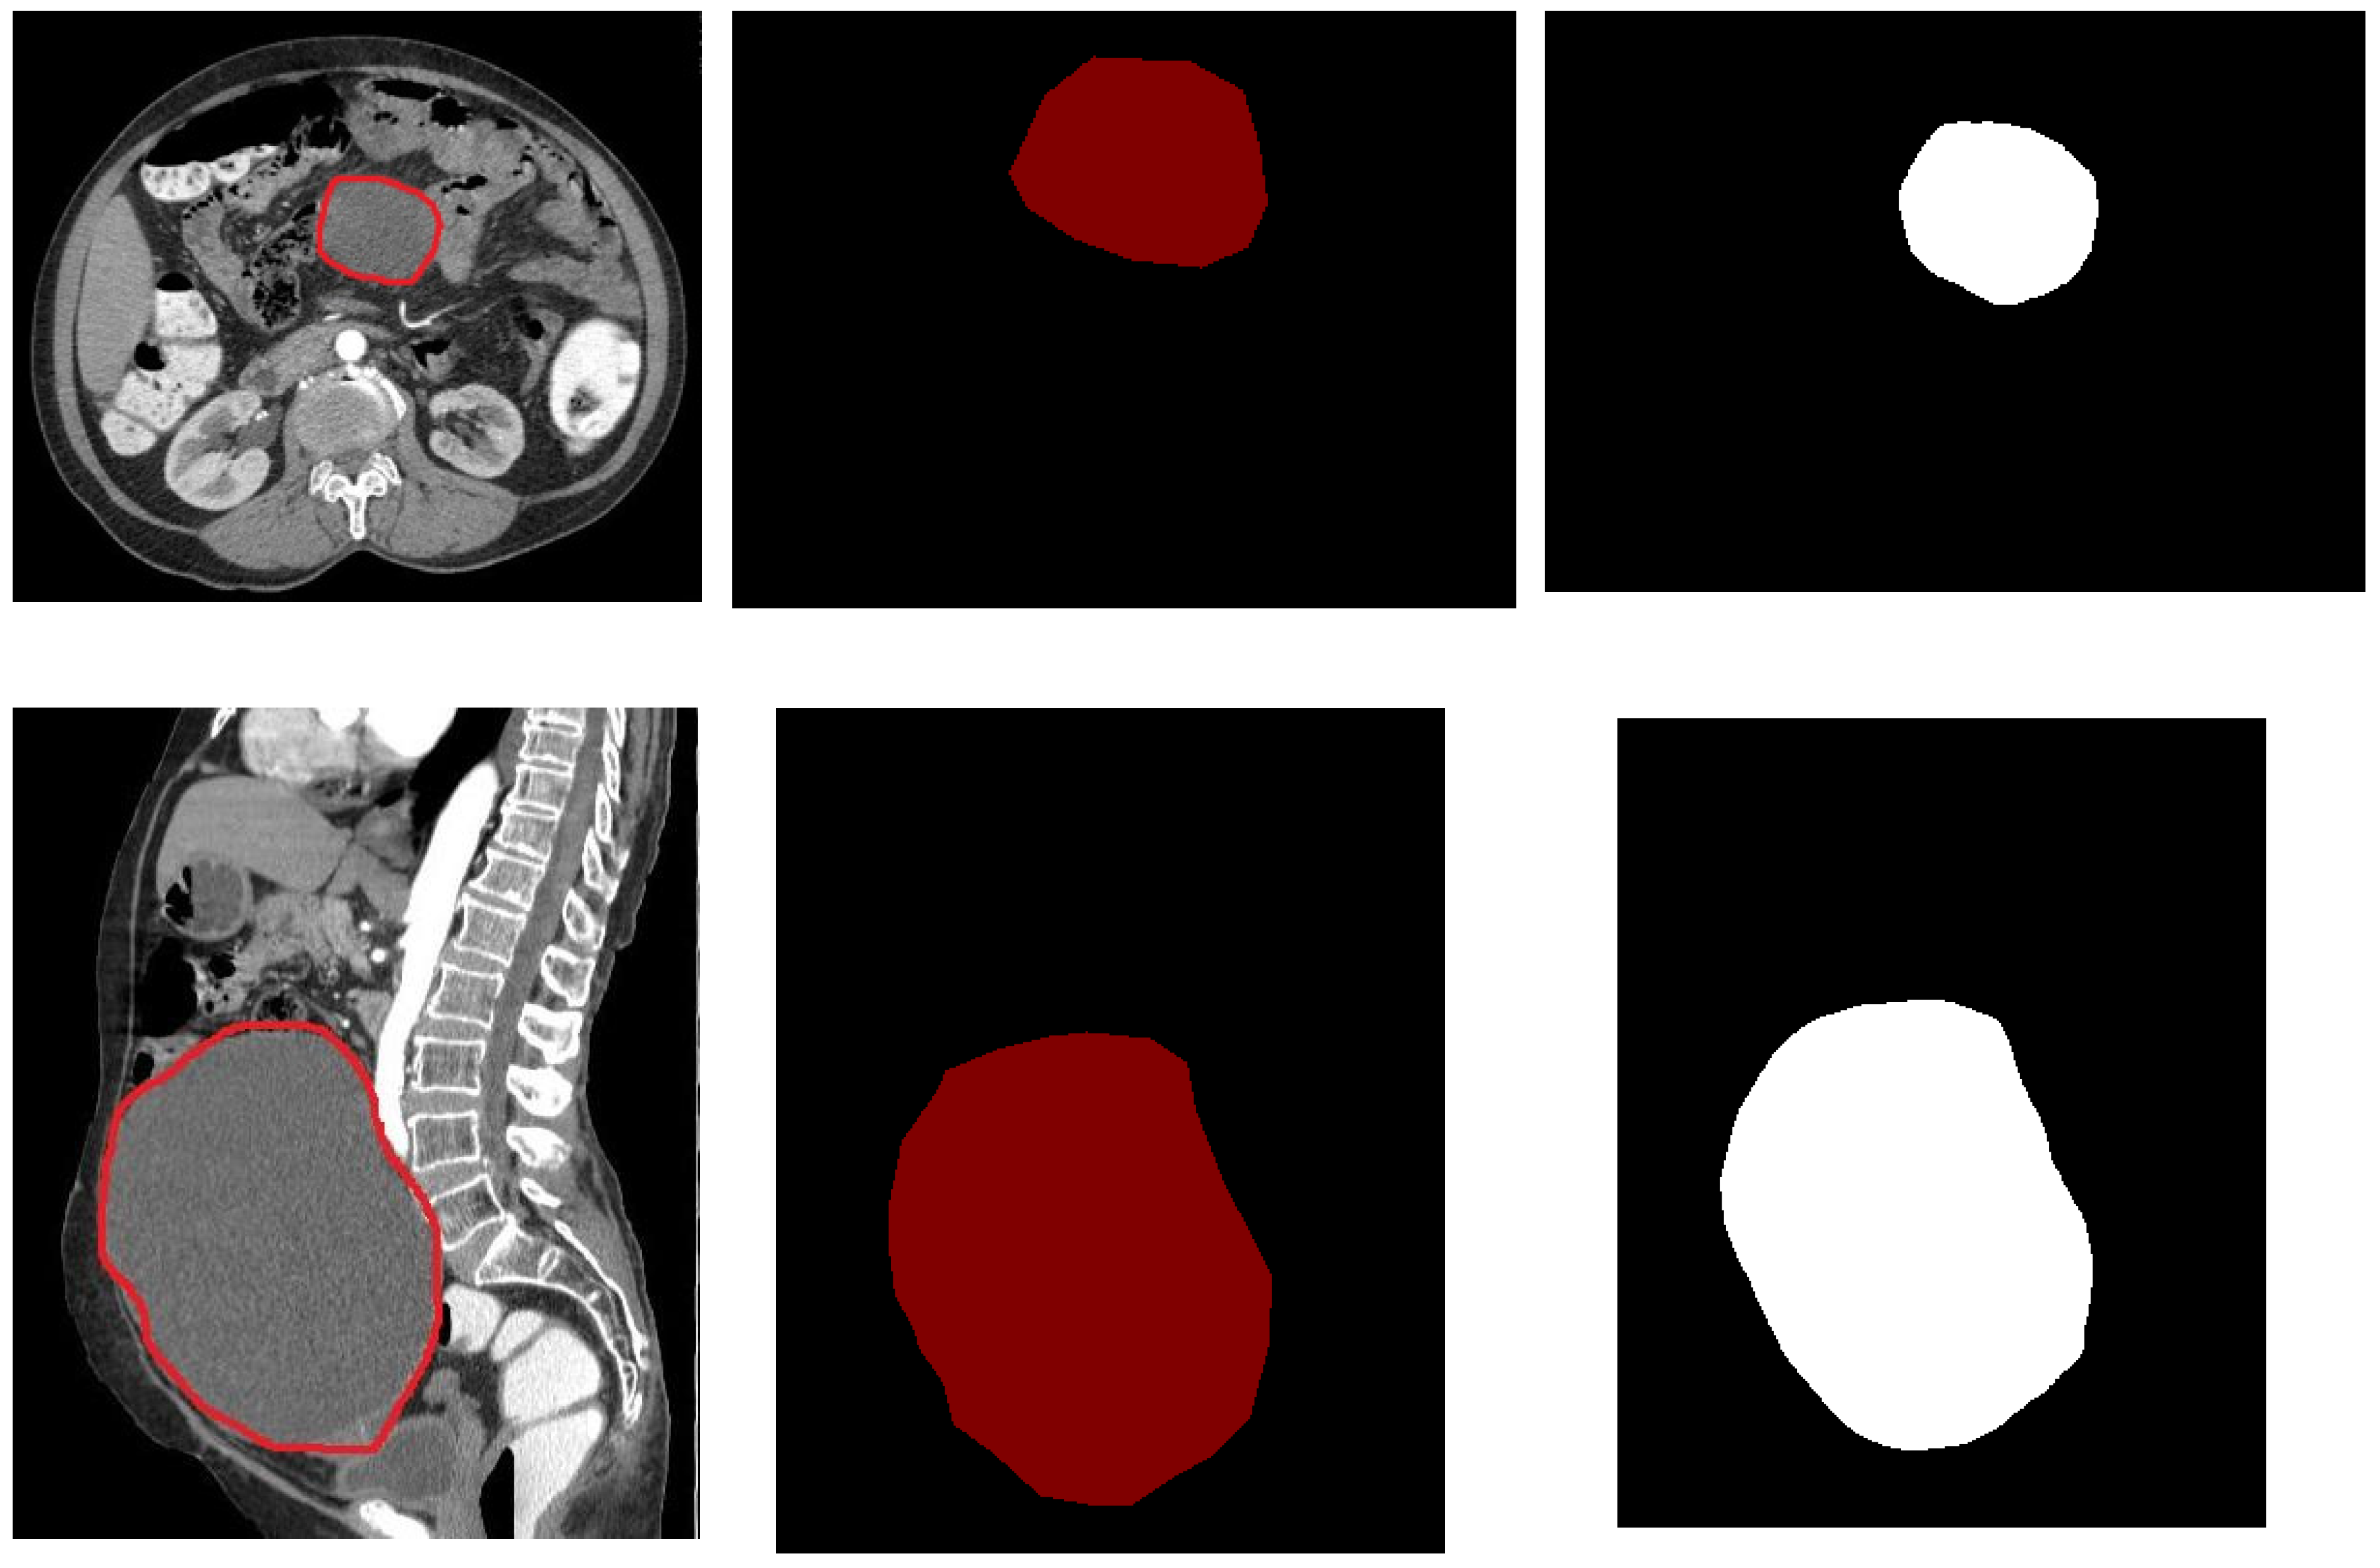

3.2. Segmentation Using U-Net Model

4.2. Segmentation Results Using the UNet Model